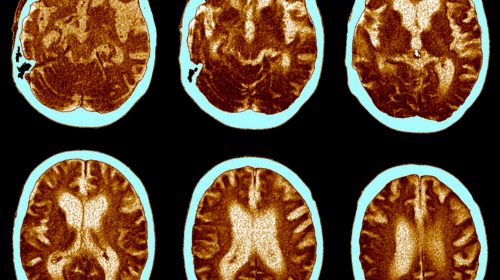

El potencial del CBD en el tratamiento de enfermedades neurodegenerativas

Por lo que hace a las enfermedades neurodegenerativas, los profesionales de la salud han encontrado un gran aliado en el CBD por sus propiedades antiinflamatorias y antioxidantes; por su poder de actuación sobre el sistema endocannabinoide, implicado en la regulación de múltiples funciones cerebrales, como el estado de ánimo, la memoria y la neuroprotección. O, por la reducción de la excitotoxicidad, causada por la sobreestimulación de las neuronas, un proceso patológico clave en muchas enfermedades neurodegenerativas.

En este contexto, el CBD ya está jugando un papel importante en el tratamiento de enfermedades como el alzheimer, el parkinson o la esclerosis múltiple. Sobre todo por lo que hace a la reducción de los síntomas de la enfermedad que afectan al aparato locomotor. Pero, pese al prometedor futuro de este compuesto en la medicina, aún se encuentra en un estado inicial con muchas limitaciones relacionadas, especialmente, con el escenario legal del uso del cannabidiol.